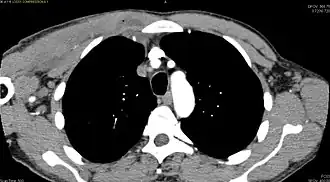

CT with IV contrast showing enlargement and heterogeneous hypodensity in the right pectoralis major muscle. A focal abscess collection with gas within it is present medially. There are enlarged axillary lymph nodes and some extension into the right hemithorax. Note the soft tissue and phlegmon surrounding the right internal mammary artery and vein. The patient was HIV+ and the pyomyositis is believed to be due to direct inoculation of the muscle related to parenteral drug abuse. The patient admitted to being a "pocket shooter" -